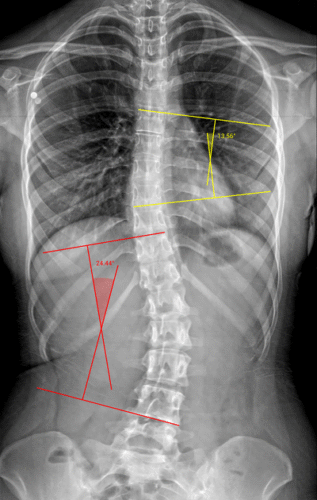

الأشعة السينية هي الوسيلة الأكثر دقة وبساطة لقياس زاوية كوب (Cobb angle)، وهي المقياس العالمي لتحديد شدة الانحناء.

إذا كانت الزاوية أقل من 20 درجة → غالبًا يُكتفى بالمتابعة والتمارين.

بين 20 و40 درجة → قد يحتاج المريض للحزام الطبي.

أكثر من 40 أو 50 درجة → قد يُناقش الطبيب خيار الجراحة.

من هنا يتضح أن صورة الأشعة ليست مجرد فحص روتيني، بل خطوة أساسية لتحديد خطة العلاج المناسبة.